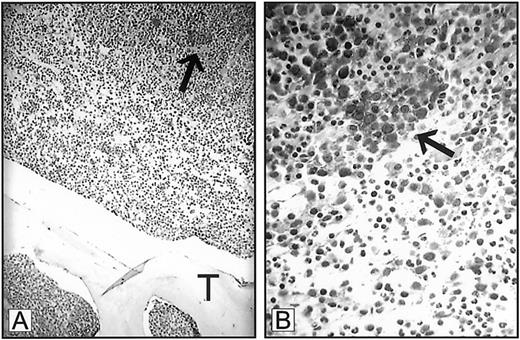

Dr Mangi interprets our data as indicating that the means by which we diagnose ALIP was based solely on findings derived from bone marrow clot sections.1-1 The definition of ALIP as originally proposed by Tricot et al1-2 1-3 resides upon resolving the spatial relationship between myeloblast clusters to bone trabeculae within trephine biopsies, as we described in “Discussion.”1(pp1432-1433) Indeed, we stress that the displacement of myeloid precursor clusters from their paratrabecular locale represents an adverse prognostic feature in MDS that is associated with an imminent risk for leukemic transformation. We do not, however, base a diagnosis of ALIP on bone marrow clot sections alone. All myeloblast clusters identified in marrow clot sections were confirmed by trephine biopsy prior to immunohistochemical staining. Our use of bone marrow clot sections to examine VEGF and receptor expression was predicated on the superior staining characteristics of bone marrow clot sections as compared to cores under the conditions used for staining in this study. Nevertheless, Mangi's letter now prompts us to include a figure showing VEGF expression in ALIP in a bone marrow trephine biopsy. Although the level of staining is not as optimal as that observed in the clot sections provided in the original manuscript, VEGF expression is clearly demonstrated (Figure1-1).

Expression of VEGF in ALIP.

Bone marrow trephine biopsy from a patient with myelodysplastic syndrome demonstrating expression of VEGF in myeloblast clusters (arrows). T indicates trabecular bone. Panel A, 250 × magnification; panel B, 1000 × magnification.